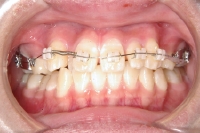

• 上顎の内側に装置

上顎の外側にセラミックブラケットを装着

下顎の奥歯にバンドを装着

• 下顎の外側にセラミックブラケットを装着